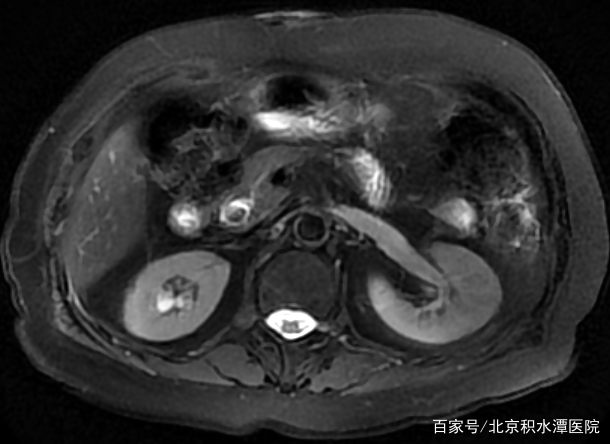

胆管结石患者核磁检查提示胆管末端存在结石